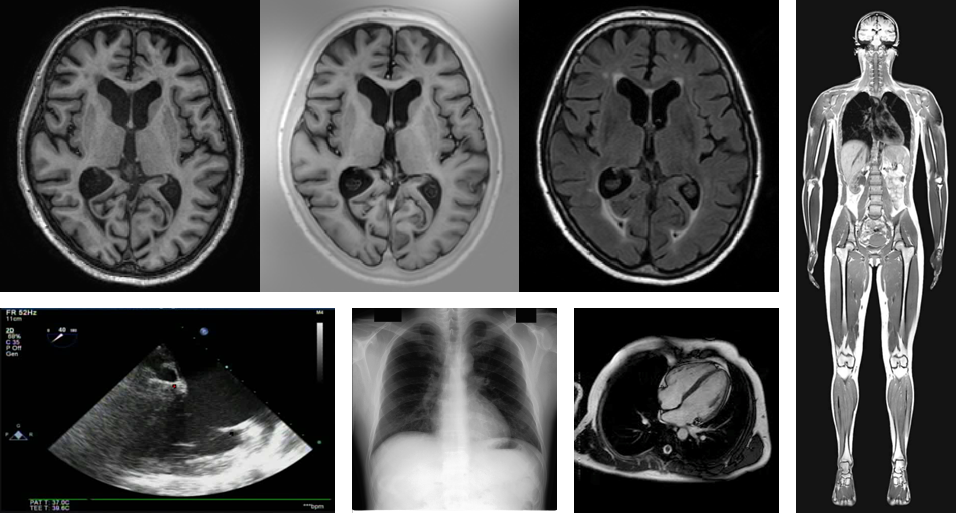

- 应用:广泛应用于肿瘤检测、心血管疾病诊断、神经系统疾病评估等领域。

医学影像技术示例